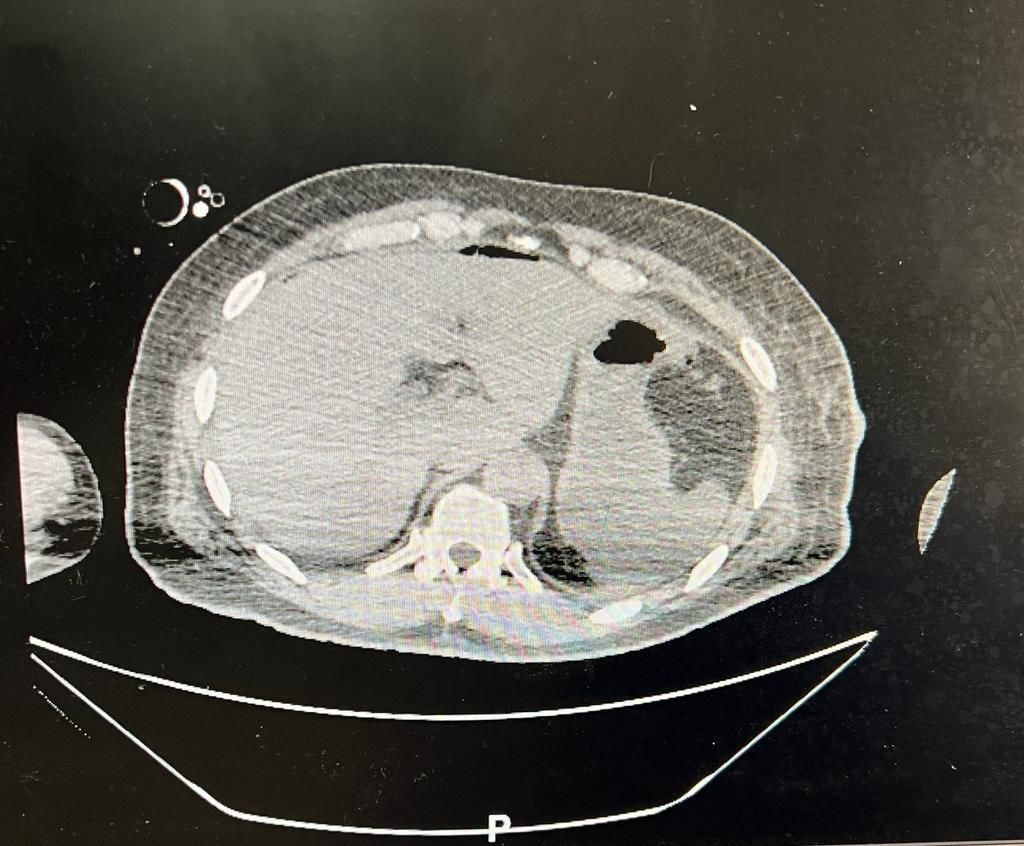

وأوضح استشاري الجراحة العامة الدكتور محمد مرزا أن المصاب حضر الى قسم الطوارئ والحوادث في حالة حرجة وهو يعاني من اصابة إثر تعرضه لطعنات بآلة حادة مع هبوط حاد في ضغط الدم، وعلى الفور تم نقله الى غرفة العمليات كحالة إنقاذ حياة وأجريت له عملية استكشافية للبطن بمشاركة قسم التخدير وأتضح وجود قطع في عضلة الكتف ونزيف داخلي ونزيف شديد في الطحال والبنكرياس والاثنا عشر مع إصابة في القفص الصدري.

وأجري للمريض عملية استئصال للطحال وخياطة العضلات والجلد للكتف والسيطرة على النزيف الدموي في التجويف البطني والصدر وإيقاف نزيف البنكرياس والاثنا عشر.